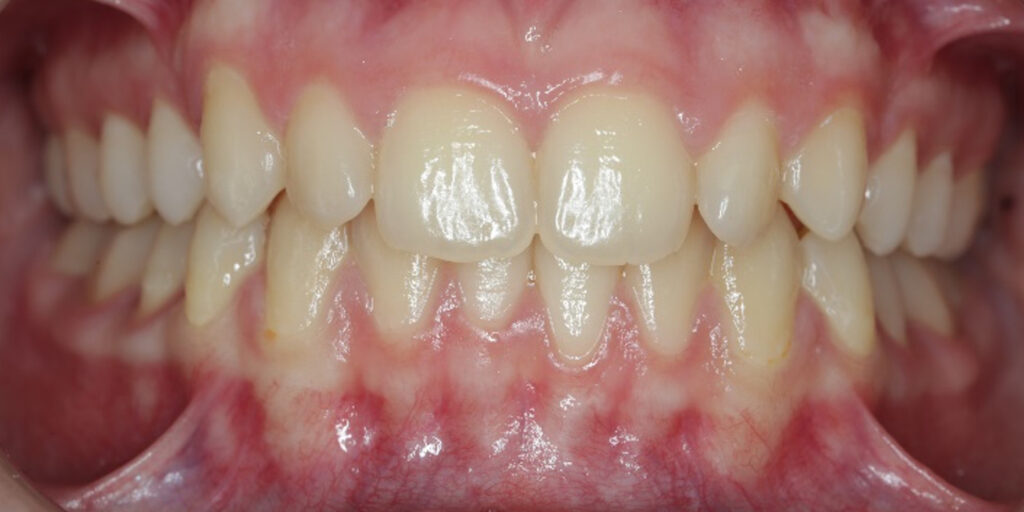

The 14-year-old female patient visited the orthodontic practice in February 2021. The chief complaint was that her upper arch was affecting her confidence in her smile. Upon examination, the patient was found to have a normodivergent facial pattern and a skeletal class II with mandibular retrusion. An intraoral examination revealed narrow arches, a class II molar and canine relationship, deep bite, retroclined upper and lower incisors, and retained teeth 63, 74, and 84.

After undergoing maxillary expansion, Dr. Sorina Blaj assessed the patient again in September 2021, and at that point, tooth 84 had exfoliated, tooth 44 had erupted, and tooth 23 had started to erupt.